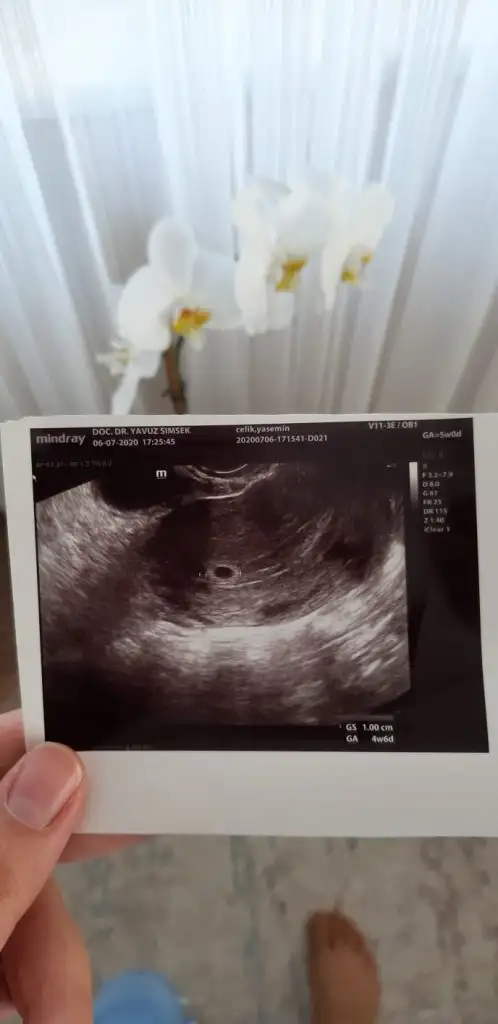

Sat a göre 6 ama dr 5+2 olabilir bir sonraki kontrole göre net soyleyecekmis boyuna bakarak yani suan beklenen doğum bir hafta ötelenecek kese boyu 8,5mm geldi